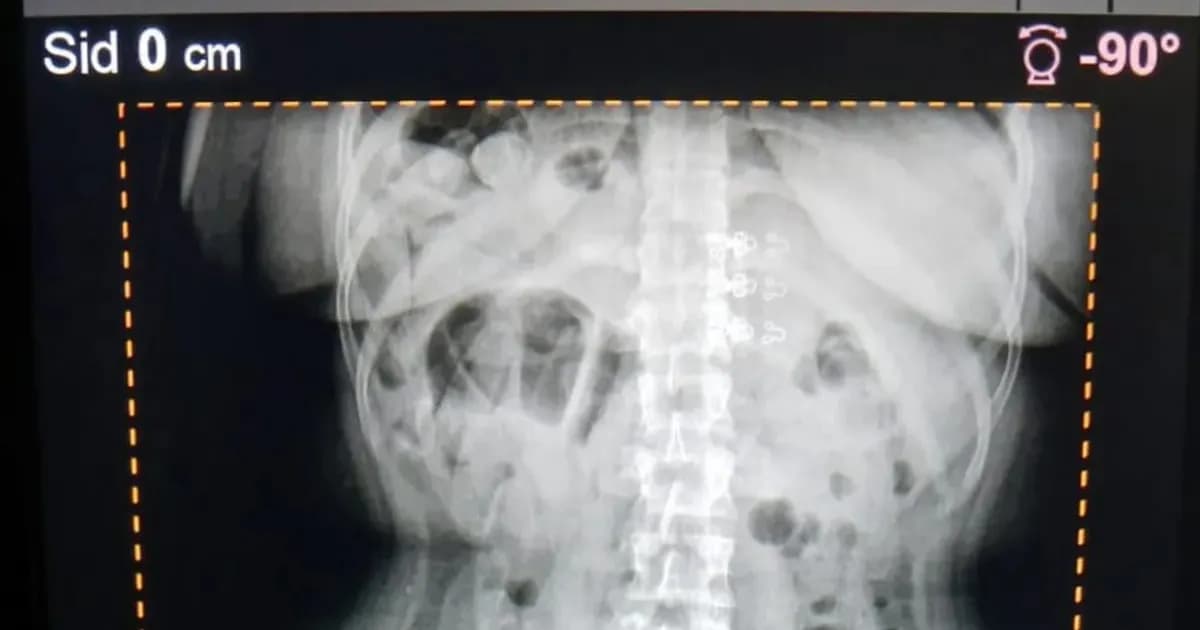

Durante una inspección de rutina, las pasajeras mostraron signos de malestar abdominal, lo que llevó a los gendarmes a sospechar de su situación. Posteriormente, fueron trasladadas al Hospital de Trancas para realizar estudios radiográficos. La intervención fue ordenada por efectivos de la Patrulla Eventual “Trancas”, parte del Escuadrón 55 “Tucumán”, que investigaban un posible caso de narcotráfico.

La investigación, bajo la supervisión del Juzgado Federal N° 1 de Tucumán, resultó en la incautación de 198 cápsulas de cocaína, confirmadas mediante pruebas de campo. Este caso pone de relieve el uso de rutas del norte argentino hacia Cuyo para el tráfico de estupefacientes. La técnica empleada por las detenidas, conocida como “capsuleras”, consiste en ocultar sustancias ilegales dentro del cuerpo para eludir controles durante traslados interprovinciales, una práctica que presenta graves riesgos para la salud de quienes la llevan a cabo.